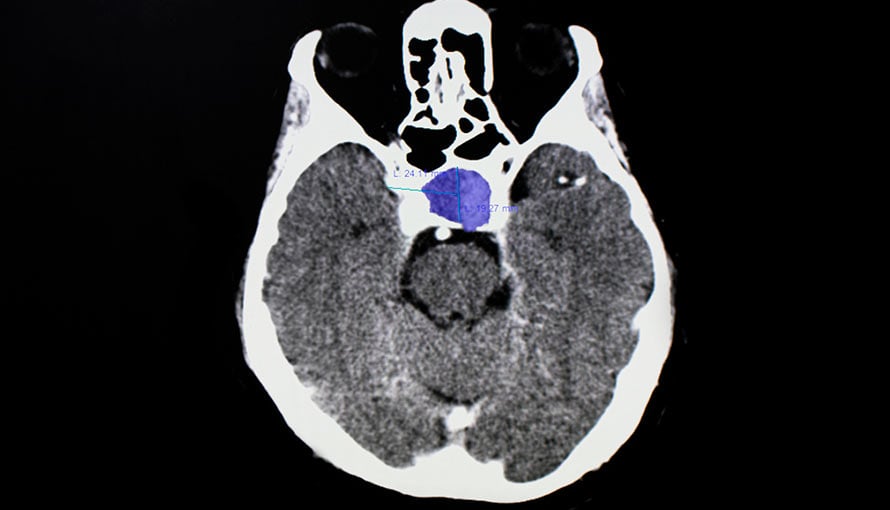

Pituitary adenoma is a benign (noncancerous) tumor that develops in the pituitary gland. This gland sits behind the eye and plays a key role in regulating hormones to help keep the body in balance.

Pituitary adenomas can be classified as nonfunctioning or functioning. A nonfunctioning adenoma does not produce hormones and a functioning adenoma does. Treatment for pituitary adenoma varies based on if it’s nonfunctioning or functioning as well as the patient’s health history.